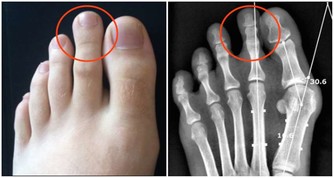

兒童期超重、肥胖會增加高血壓、糖尿病、高甘油三酯、代謝綜合徵等的發生風險,肥胖還會影響兒童青春期發育,危害呼吸系統及骨骼,甚至對心理、行為、認知及智力產生不良影響。